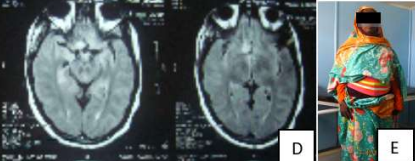

Sixty years old housewife, presented complaining of amnesia, disorientation, right side heaviness and headache for one month, which was of progressive course.

On examination she looked ill and confused with grade 4 right sided weakness. MRI of the brain showed left frontal Brain tumor. The tumor was totally resected through left frontal craniotomy ,histopathology result was grade one meningioma, the patient showed full recovery one year post-operative.

Image (A) Preoperative MRI showing the left frontal brain tumor

Image (B) is an operative image after total resection of the tumor, Image (C) is post-operative MRI showing no evidence of residual tumor, Image (D) is the patient after full recovery one year post-operative.